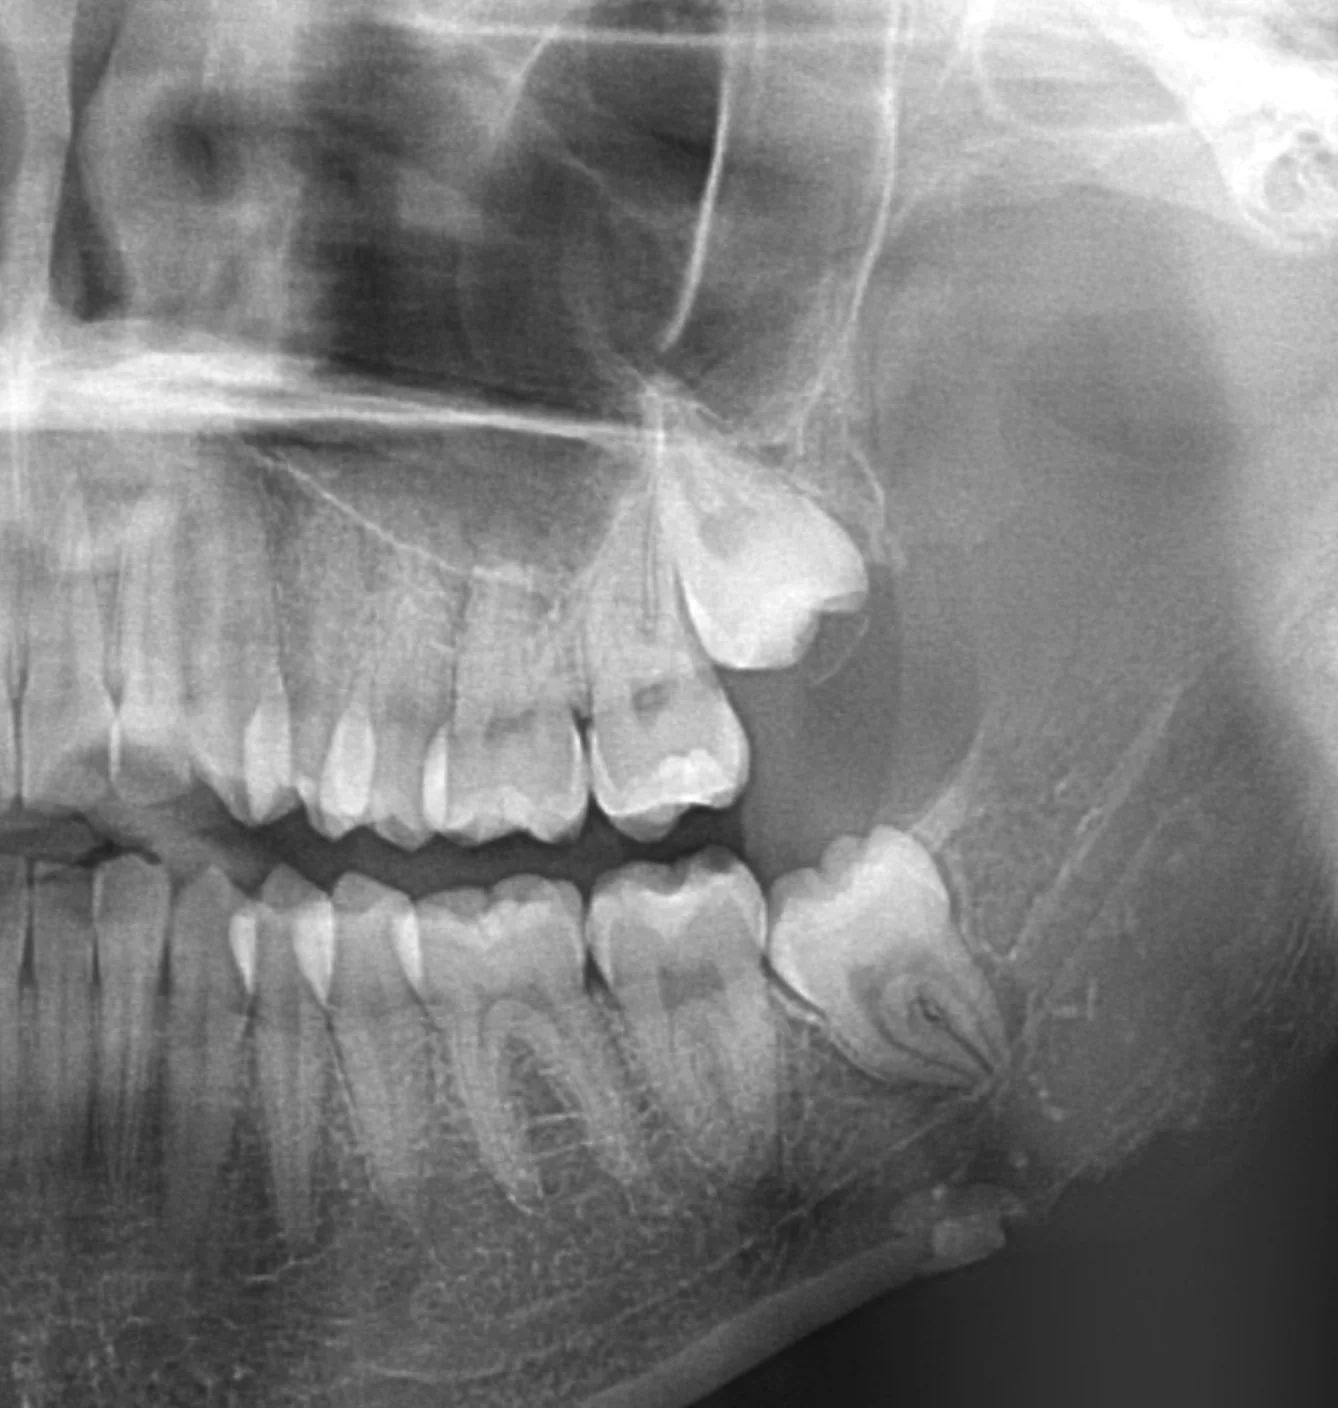

- Referral and Imaging: The process begins with a referral from your dentist, along with a recent OPG X-ray. Dr Henze’s team can arrange a request form for you to have this completed at SKG Radiology. An appointment is not required for the OPG. X-rays are used to assess the position and condition of the wisdom teeth.